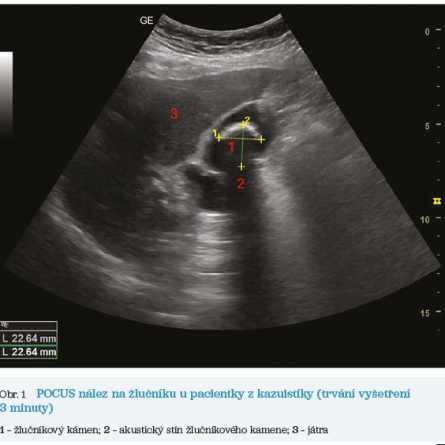

Obr. 1 POCUS nález na žlučníku u pacientky z kazuistikyPři příchodu do ordinace byla pacientka eupnoická, bez ikteru, s tělesnou teplotou 36,5 °C. Výsledek fyzikálního vyšetření byl jinak normální včetně poslechového a poklepového nálezu na plicích, akce srdeční klidná, tepová frekvence 65/min, bez šelestu, tlak krve 135/85 mm Hg, saturace arteriální krve kyslíkem 99 %, břicho nad niveau, měkké, prohmatné, nebolestivé, bez palpační citlivosti v pravém podžebří (Murphyho příznak negativní), bez známek náhlé příhody břišní, tapotement oboustranně negativní, C‑reaktivní protein POCT (Point‑of‑Care Testing) 12 mg/l, moč chemicky negativní, EKG (elektrokardiografické vyšetření) s fyziologickou křivkou. Součástí klinického vyšetření bylo i vyšetření žlučníku metodou POCUS (obr. 1) s nálezem viditelného hyperechogenního útvaru s akustickým stínem bez známek zánětlivých změn stěn žlučníku. Čekací doba na tradiční ultrasonografické vyšetření břicha a ledvin byla v daném regionu v daném období osm týdnů. Byla stanovena pracovní diagnóza žlučníkového kamene (cholecystolitiáza).